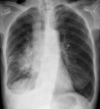

**Heart failure** Alveolar batwing shadowing Kerley B lines Cardiomegaly Upper lobe Diversion Pleural Effusion

39